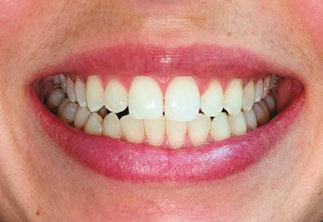

Upon completion of MFT and active treatment phase with clear aligners (Figures 12, 13, 14, 15, 16), the patient revealed that snoring significantly reduced, her partner does not complain anymore, and she is breathing through the nose 75% of the time. The patient is holding her lips together 75% of the time and is able to keep her tongue on the spot 50% of the time.

Figure 12: Anterior view upon the completion of active treatment

Figure 17: Smile upon the completion of active treatment

Figures 13 and 14: 13. Right side upon the completion of active treatment. 14. Left side upon the completion of active treatment

Figures 15 and

15. Occlusal view upon the completion of active treatment. 16. Lower occlusal view upon the completion of active treatment